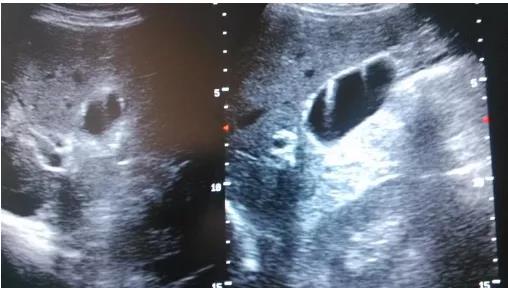

(▲膽囊假性息肉)

所以不是所有的息肉都是真的,假性息肉和癌沒啥關(guān)系,真正要關(guān)注的是:真性息肉!

(▲膽囊真性息肉)